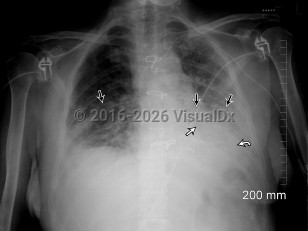

LegionellosisLegionellosis